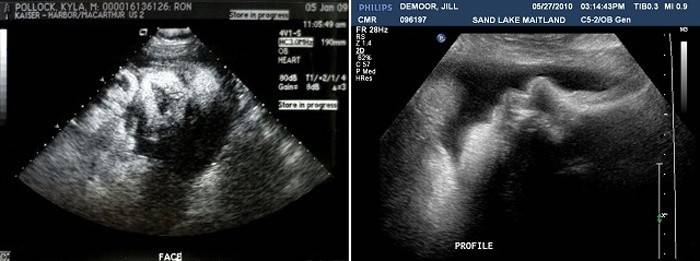

Ультразвукове дослідження (Узд)

На цьому терміні планові УЗД вже не проводяться, на лікар може призначати УЗД для вирішення невідкладних питань при плануванні кесаревого розтину або для вирішення питання про ведення пологів. Зазвичай УЗД призначають при попередніх дослідженнях з виявленням обвиття пуповиною, а також для визначення кількості навколоплідних вод, стану плаценти, її зрілості і розташування плода в матці, шийки матки. Також проводиться і оцінка розвитку плода, його приблизна маса зростання, уточнення ПДР за даними УЗД. Важливо визначити розмір голівки і грудки плоду, довжину великих кісток.

Також в 38 тижнів за даними УЗД визначають розміри шийки матки, її зрілість та стан готовності до пологів.